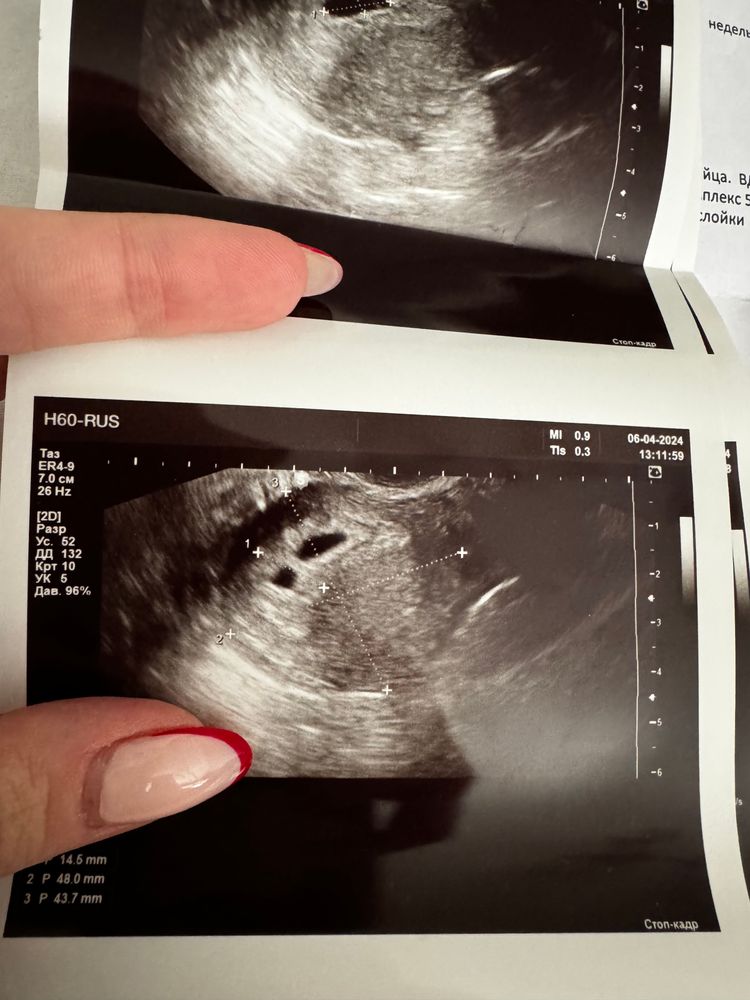

Яркость, 2 посадили на прогик… одна по анализу, где все ок, вторая по ЧСС, хотя по нормам ВОЗ ЧСС на этом сроке может не быть, а для моего возраста, при наличии у эмбриона ЧСС 109+-14. Попробую поискать хорошего врача в Москве, но эти в топе на докдок 🫠